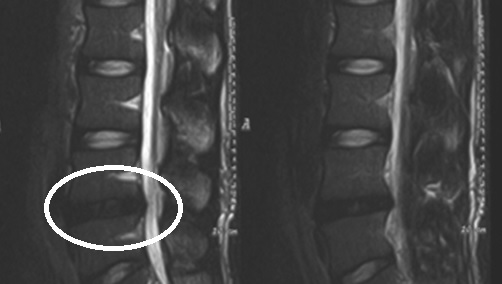

디스크 변형: 디스크 손상이 지속되면 디스크의 변형이 발생할 수 있습니다. 이는 척추의 안정성을 감소시키고 주변 신경과 조직에 압박을 가할 수 있습니다. 디스크 변형은 통증, 피로, 근육 약화 등의 증상을 유발할 수 있으며, 일부 환자는 디스크 수술을 필요로 합니다

척추 디스크 질환의 진단은 종종 신체검사와 환자의 증상 및 병력을 바탕으로 합니다. 추가적인 검사는 X선, MRI, CT 스캔 등을 포함할 수 있습니다.

디스크가 변성되었다고 하는데 무슨 말인가요??

(디스크변성증, 디스크 내장증)